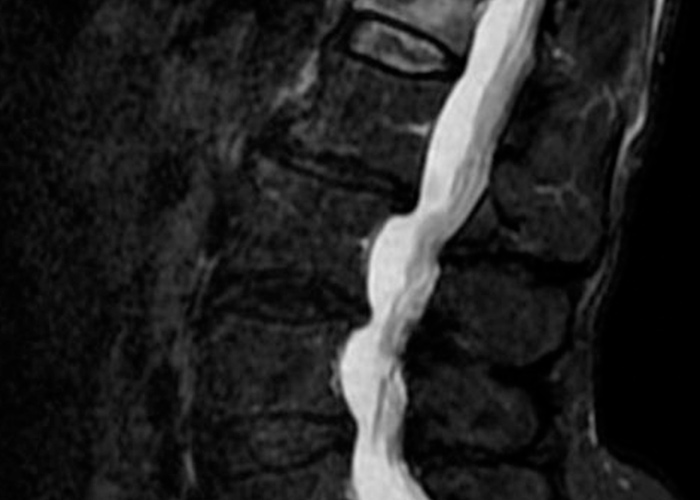

postoperatorio-cifoplastia-madrid

Postoperatorio

Con esta técnica la recuperación es prácticamente inmediata.

El dolor desaparece inmediatamente.